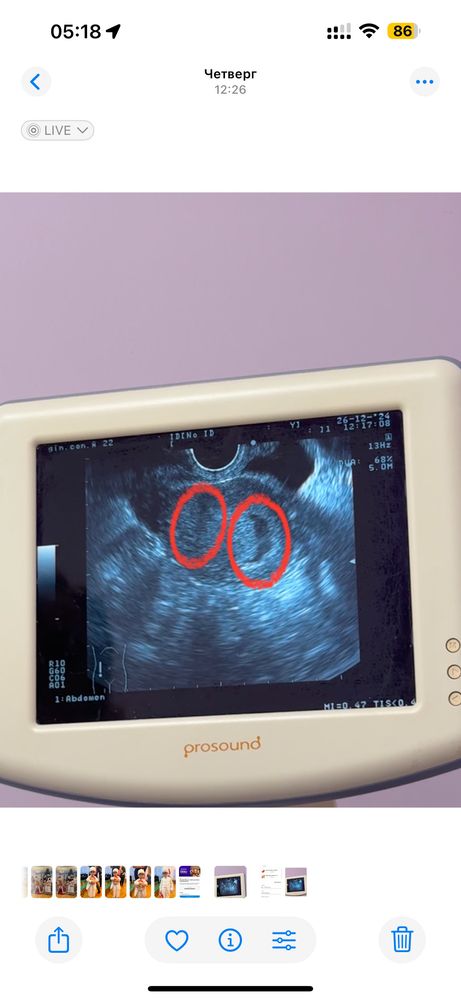

Беременность 5 недель

Многоплодная беременность

ничего не понимаю, узнала, что беременна, пошла к гинекологу, отправили на узи, показало, что есть одна беременность, но, когда я сфоткала и пересмотрела фото, ничего не поняла, либо мне кажется, либо так и есть, там двойня?😳

справа точно малышок есть, а что слева, мне не понятно, увидела только уже дома(

Одно плодное яйцо. Видимо, у вас тонус, оно деформировано.

у вас одно плодное яйцо. Второе что вы обвели - могут быть вены, сосуды или что-то такое.